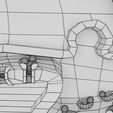

神经肌肉接头示意图